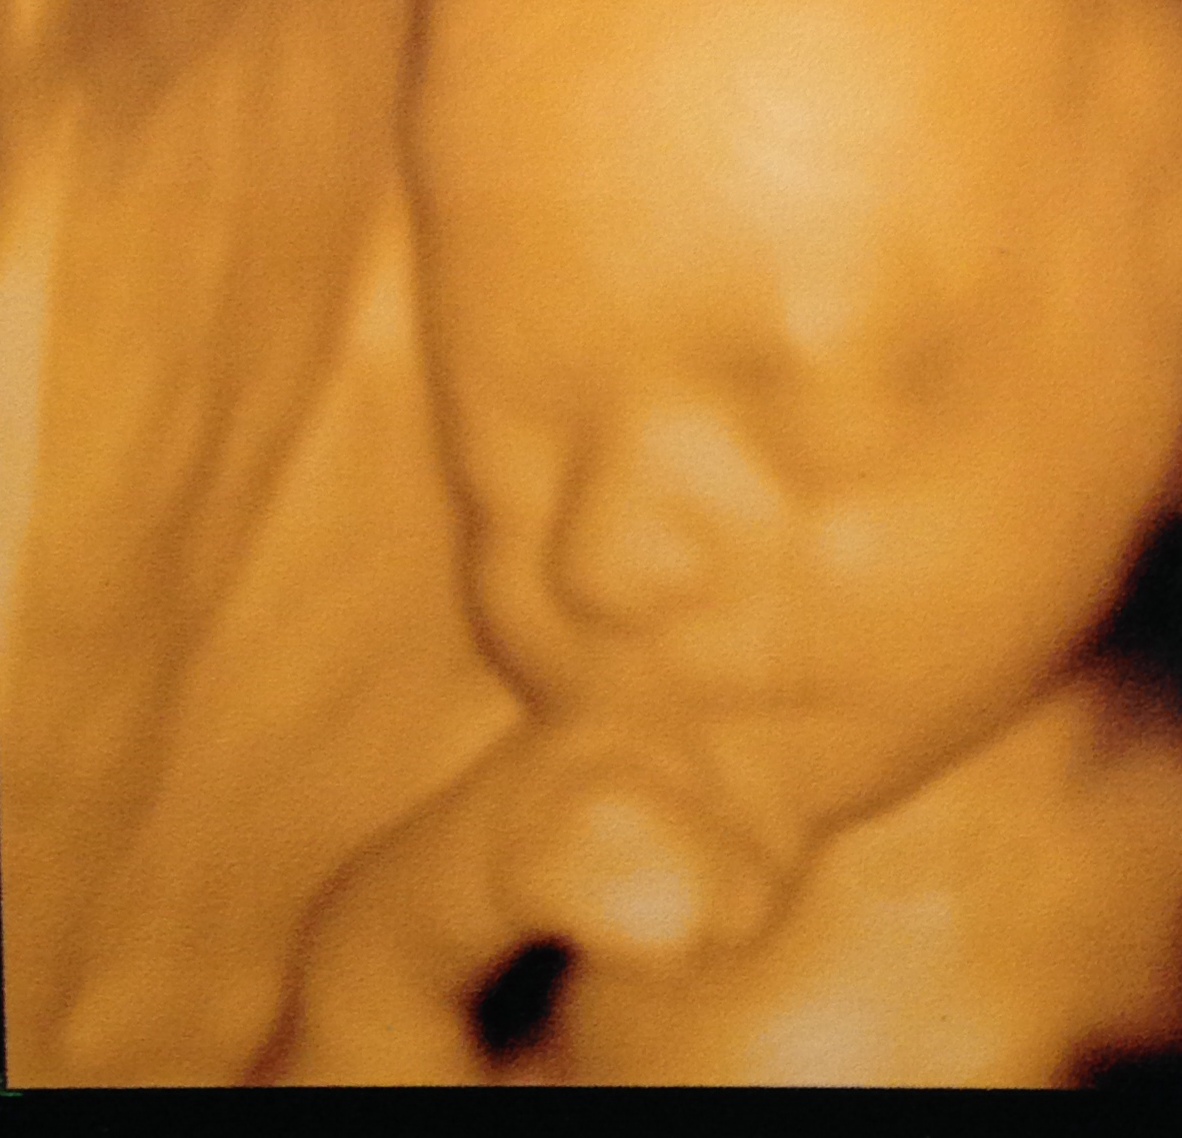

(and yes, these are actual 3D ultrasound pictures of Ella – she looks great already!)

Yes! And we think she has Bart’s “pointier” nose and my connected earlobes ;) Oh, modern technology.